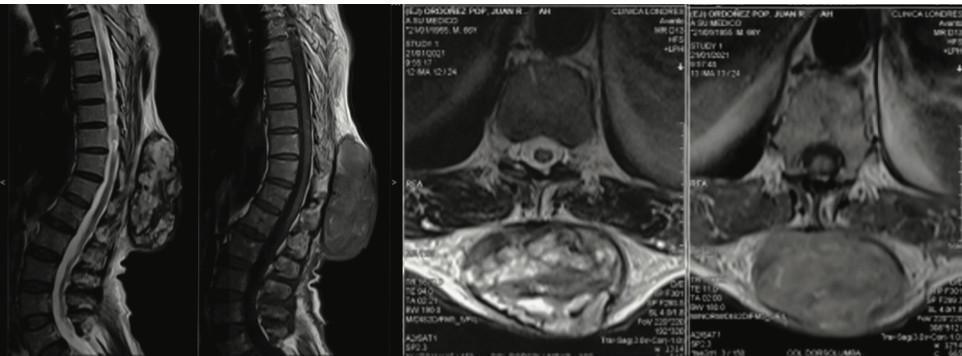

Resonancia magnética de columna dorsal: a nivel de te- jidos blandos de la región dorsolumbar a nivel de T10-L1 se observa masa heterogénea con áreas de necrosis, así como áreas solidas que mide 12.2x5cm (figura 3).